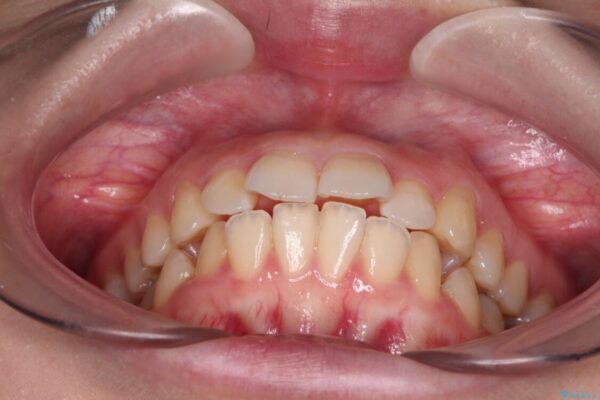

上下の前歯が突出しており、口が閉じにくいとのことで来院された患者様です。

上下前歯が著しく前突している状態であったので、上下左右の第1小臼歯4本を抜歯し、ワイヤー装置にて矯正治療を行うこととしました。

治療前